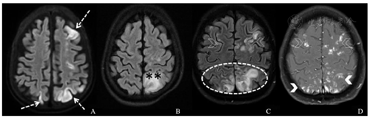

临床上最常用的脑影像学辅助诊断方法为头颅磁共振成像(magnetic resonance imaging,MRI)和头颅CT。头颅CT操作简便,对颅内出血、大面积脑梗死和较大脓肿灶敏感,可用于排除其他神经系统病变。头颅MRI,尤其是磁共振扩散加权成像对脑内细胞毒性水肿和血管源性水肿具有更高的特异性和敏感性,可发现脑内微脓肿灶。但部分患者因病情过重或出现谵妄而难以配合检查。研究发现,SAE患儿头颅MRI常表现为异常脑白质高信号、多发性缺血性卒中、内皮或内皮下出血或血肿、血管源性水肿、弥散性脑微脓肿,少数患儿可见脑萎缩和轴索损伤(图1、图2)[17,18,19,20],因此头颅MRI对SAE患儿诊断价值更高。根据脑白质高信号分级,SAE患者以2、3级多见,磁共振液体衰减反转恢复序列增强[18]。弥散性MRI急性变化也可以提示另一种特殊的脑损伤,即可逆后部脑病综合征(posterior reversible encephalopathy syndrome,PRES)。SAE是PRES的最常见病因之一,PRES可以看做SAE的一种特殊并发症,出现PRES的SAE患者常表现为全身性癫痫发作,少见或无高血压[21]。

A:虚线箭头处为双侧大脑半球前、后分水岭区弥散受限,代表分水岭梗死。B:图示左侧顶叶皮质及皮质下白质内非特异性T2信号高信号融合区(**),左侧额叶后周区可见散在微小高信号灶。C、D:液体衰减反转恢复高信号在皮质和皮质下区域(虚线椭圆形)汇合,顶叶(实箭头)结节性增强灶,特征符合可逆后部脑病综合征;额叶左侧比右侧多见异常信号强度的散在区域(虚线箭头)。